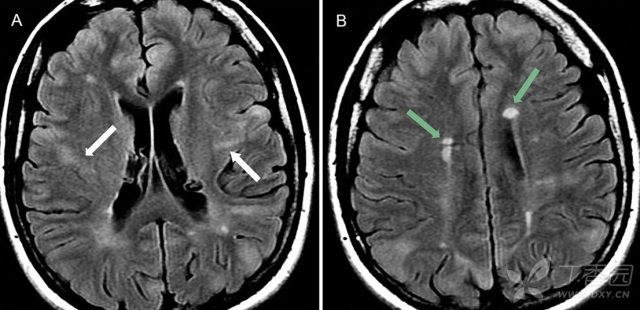

影像学上可表现为室管膜下多发结节(90%),皮质及皮质下结节(70%),脑白质异常信号和室管膜下巨细胞星形细胞瘤。室管膜下多发结节常发生于尾状核的表面,位于室管膜下,呈对称或不对称分布。T1WI 多呈等或稍高信号;T2WI 及 FLAIR 呈高信号,钙化则成低信号。增强扫描结节多强化。CT 可见典型「烛泪征」。皮质及皮质下结节 T1WI 可见结节样增厚的脑回,呈稍低信号;T2WI/FLAIR 呈高信号。增强多不强化。脑白质异常典型者可表现为「辐射带征」,即从脑室或脑室旁白质延伸至正常皮层或皮层下结节。室管膜下巨细胞星形细胞瘤为较罕见的中枢神经系统肿瘤。T1WI 呈等信号或低信号,T2WI 呈轻度至明显高信号,钙化区呈低信号。增强扫描瘤体呈明显均匀强化。可出现一侧或双侧脑室积水。

图 3:21 岁难治性癫痫伴结节性硬化症女性患者;A:FLAIR 可见高信号皮质结节伴条带状异常信号,从皮质延伸至侧脑室;B:FLAIR 可见多发高信号室管膜下结节